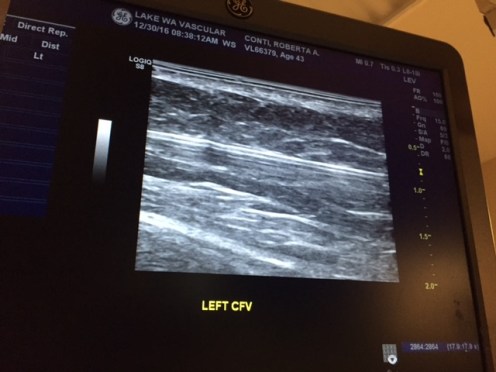

At 8:55 I was done, they put a band aid on the injection site, and washed most of the betadine off my leg. An ultrasound pass over the area to make sure there weren’t any issues, then I went to change and get my discharge instructions. No pain meds (unless I felt the need, in which case, Advil), be active (don’t sit on your butt), and if it’s going to be sore it will hit about day 5 to 10. Follow up appointment is January 11th.